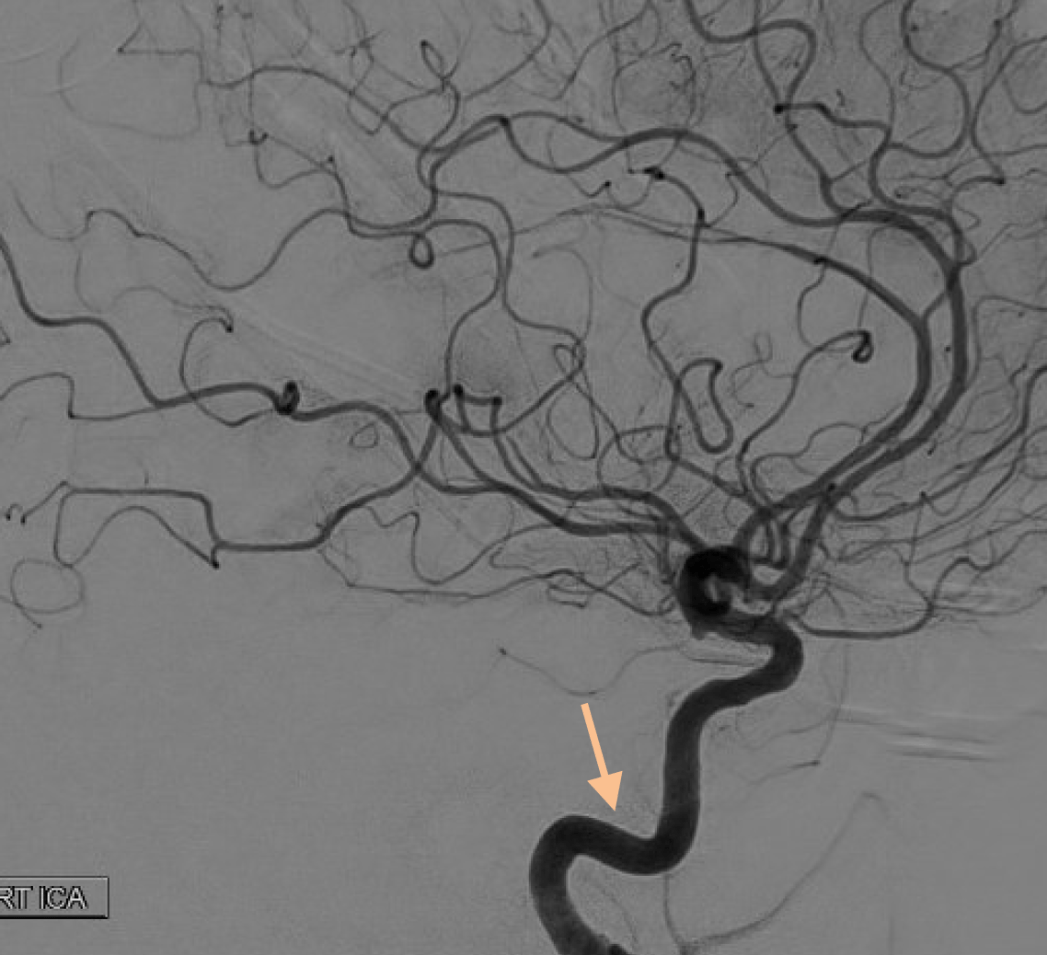

Which vessel is the arrow pointing toward?

Anterior choroidal artery